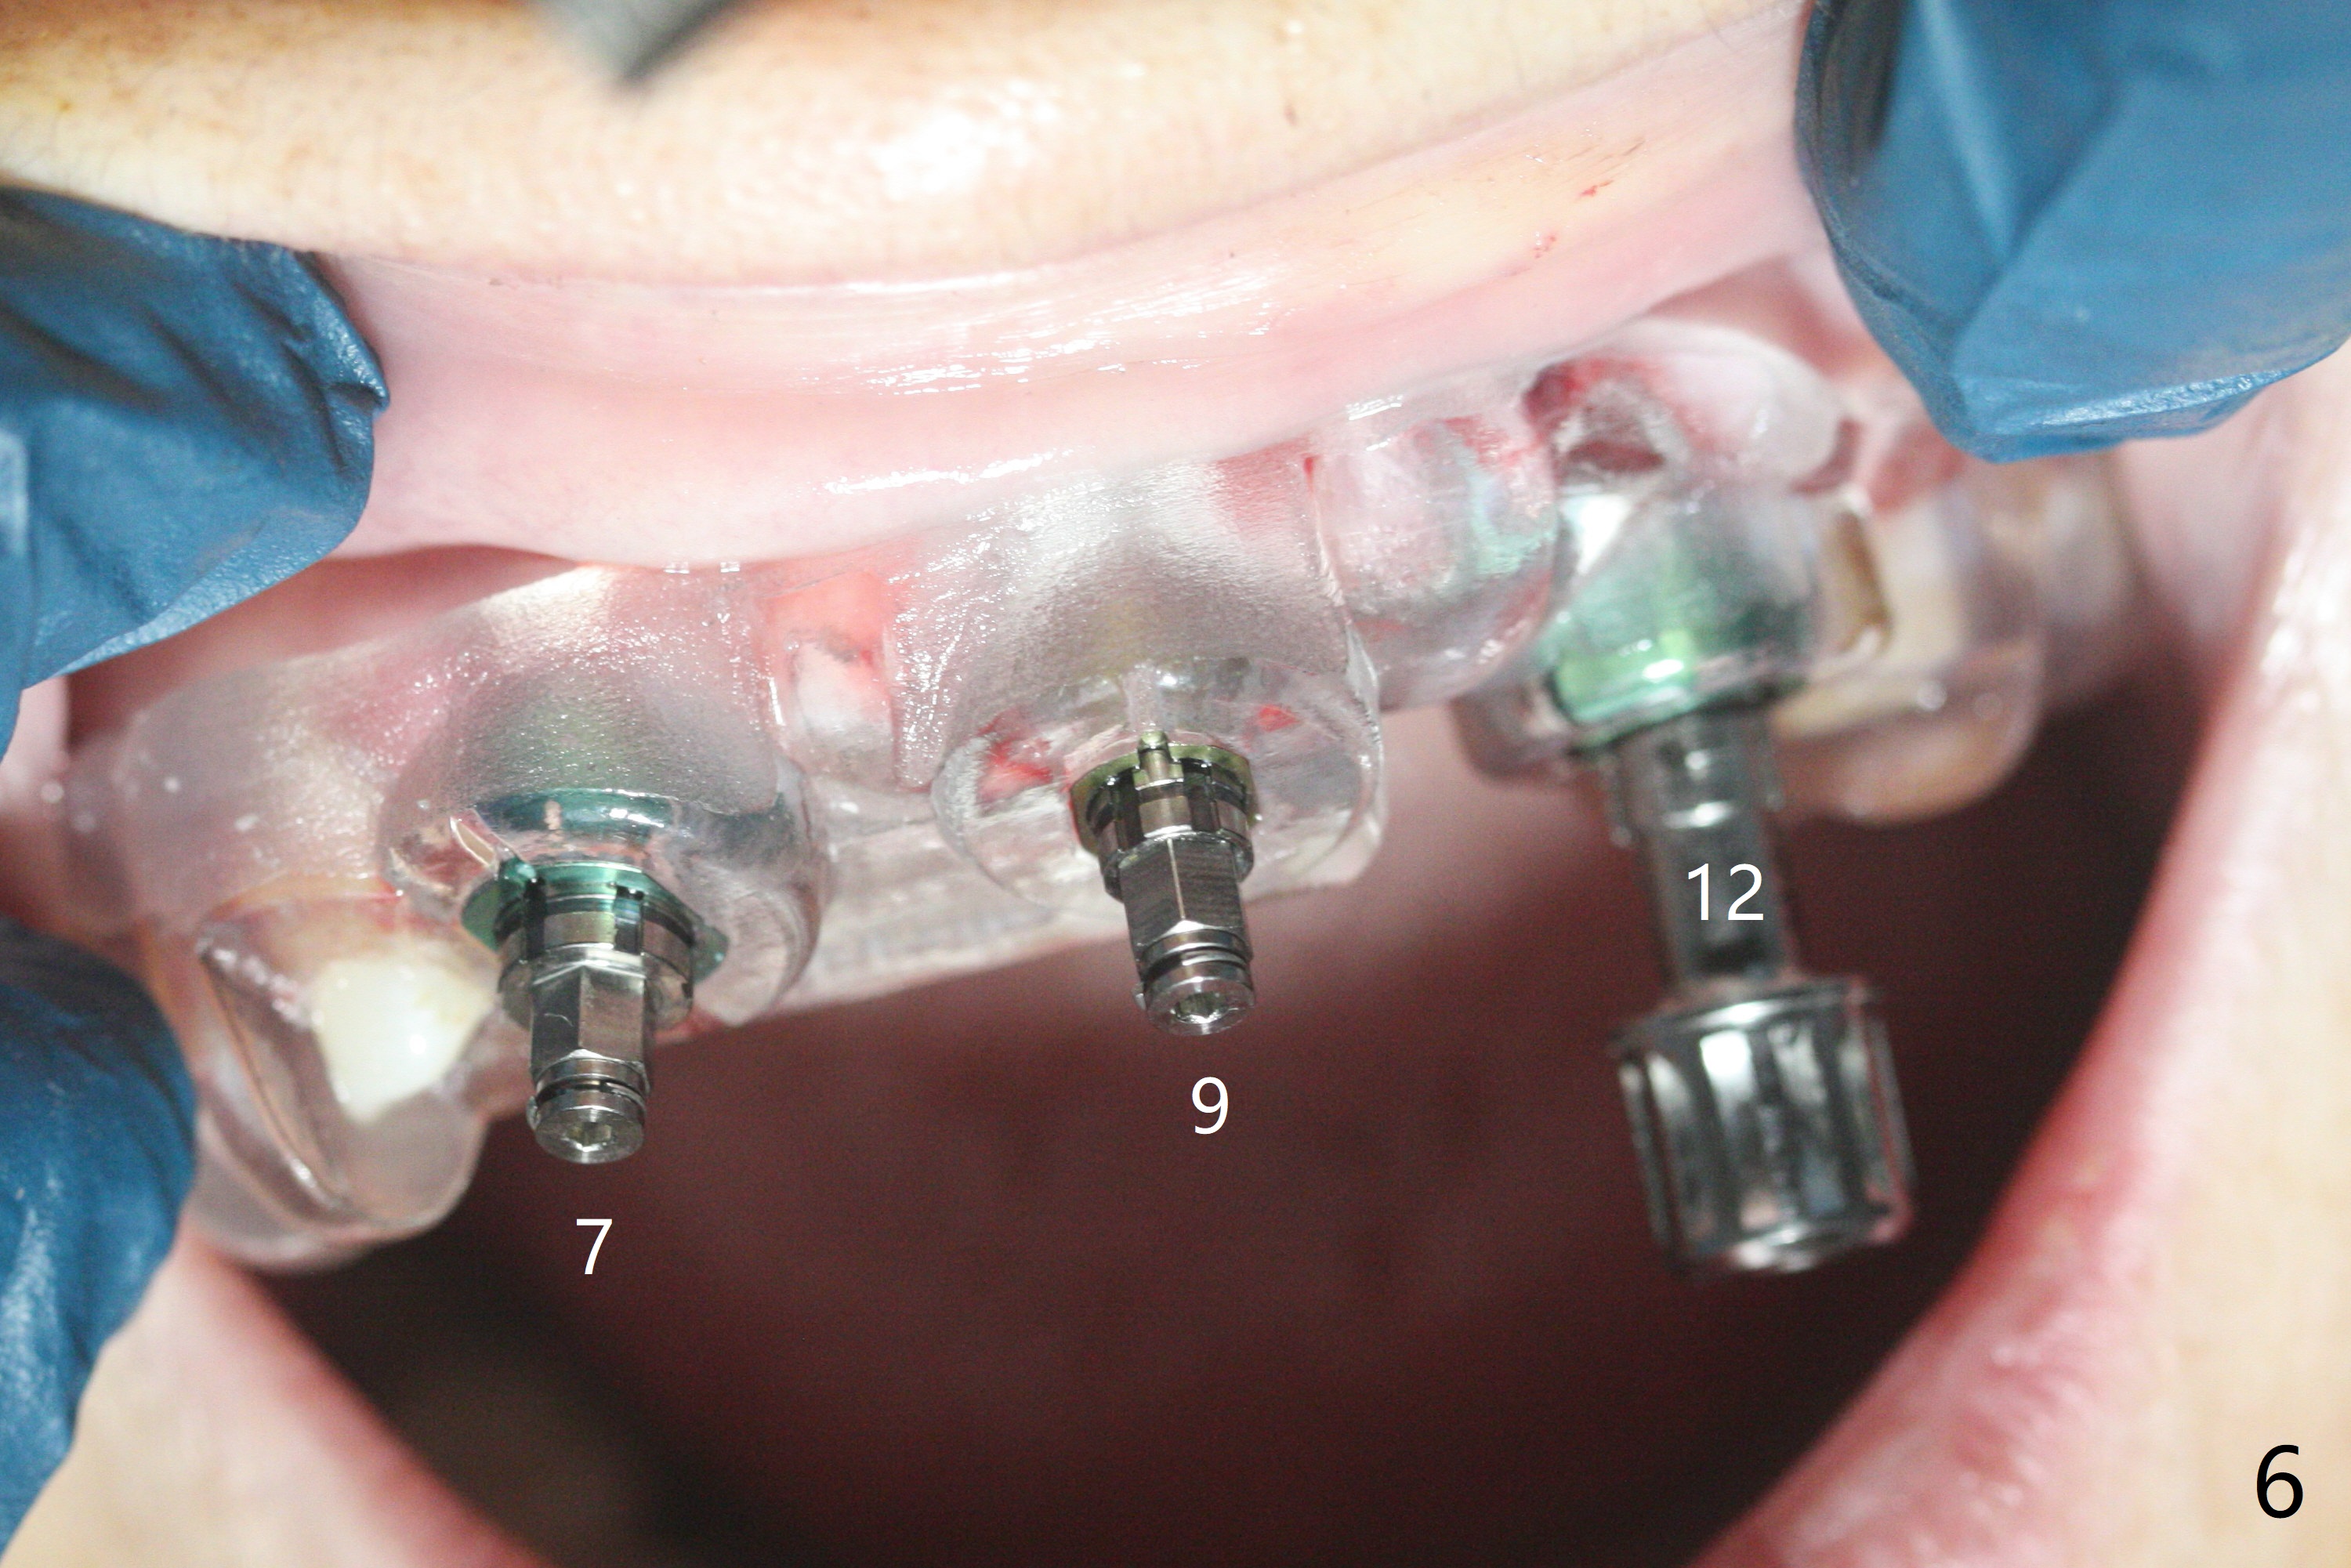

今天下午进入治疗室,粘性骨粉已制备:上清液来自红管(含促凝剂),离心3分钟(图一);再离心10分钟上清液就转变PRF,压制后,使用前剪成三块(图二:黑线),其中两块punch一个洞(图二:圆圈),插入7,9号牙基台固定;大块覆盖11/12号牙牙槽窝(图十四)。7,9,11,12号牙必须拔除(图三),然后在7,9,12种植。由于缺失左下磨牙,前牙垂直距离减少(图四)。完成9号牙位钻洞后,利用fixture mount(图五:M)植入植体,并留在原位固定导板(图六),然后7号牙种植,也留下fixture mount(图六:7,9),最后完成12号牙植入,但是后者扭力低,放置愈合螺帽(图九),而7,9号牙位放置修复基台(图七,八(使用5.5毫米profile drill后),好像基台没有完全就位。7号牙位更换基台似乎没帮助(图十),9号牙位再次放置同一个基台临床上仿佛有改变(比较图八与十二)。放置粘性骨粉后(图十一至十三),牙槽窝口覆盖PRF膜(图十四:P(A:基台)),最后使用树脂敷料固定骨粉和膜(图十五,六),基台帮助敷料固位,没有咬合干扰(图十七:*)。树脂敷料部分解决美观问题,一个月后撤除,如果植体仍有稳定性,可能制作7-10临时牙桥,可能部分维持或者恢复牙龈外形。术后一周病人主诉后面植牙和鼻底疼痛,11号牙根尖牙龈充血(图十八),轻度触痛,可能与术中尚未完全清创有关(图十九(术前CT 3D图像))。再服用Amoxicillin一周,症状好转,鼻底轻度触痛(图二十)。术后1.5月没有任何不适,撤除树脂敷料,7号牙基台(袖)显得太长,换一个短的(4.5x4(5)(图十,十一)->4x4(3)毫米)毫米),植骨好像愈合正常(图二十一:*)。7号牙换了短的基台,9号牙基台高度调整后,与对合牙有足够空间做临时牙桥,最好8,10号牙位牙龈应该凹陷(图二十二:*),有pontic外形。另外9号牙基台颊侧牙龈边缘有所修整,临时牙桥准备。先做7-10临时牙桥,理想临时牙桥pontic处树脂应该多些(图二十三:白线)压迫牙龈形成凹陷。11,12号牙牙槽窝在树脂(Bosworth)敷料下也正常愈合(图二十四)。